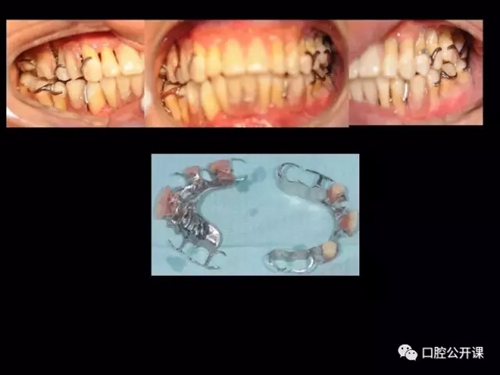

一例廣泛型侵襲性牙周炎5年臨床追蹤下

楊淑銀醫(yī)師用他的一例侵襲性牙周炎五年臨床病例追蹤來縮影一個青年牙周醫(yī)師的成長之路,帶我們一起探索看似平凡枯燥的牙周基礎治療到底有怎樣的重要性?